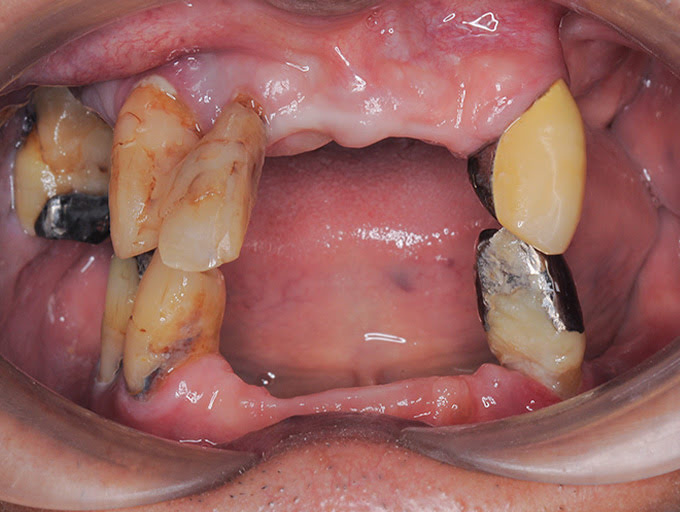

虫歯や歯周病でほとんどの歯が抜けてしまった患者さん。オールオン4治療で噛む力が回復し、美しい口元を取り戻したケース。

虫歯や歯周病で奥歯がほとんど抜けていた患者さん。オールオン4治療で、機能的にも審美的にも回復したケース。